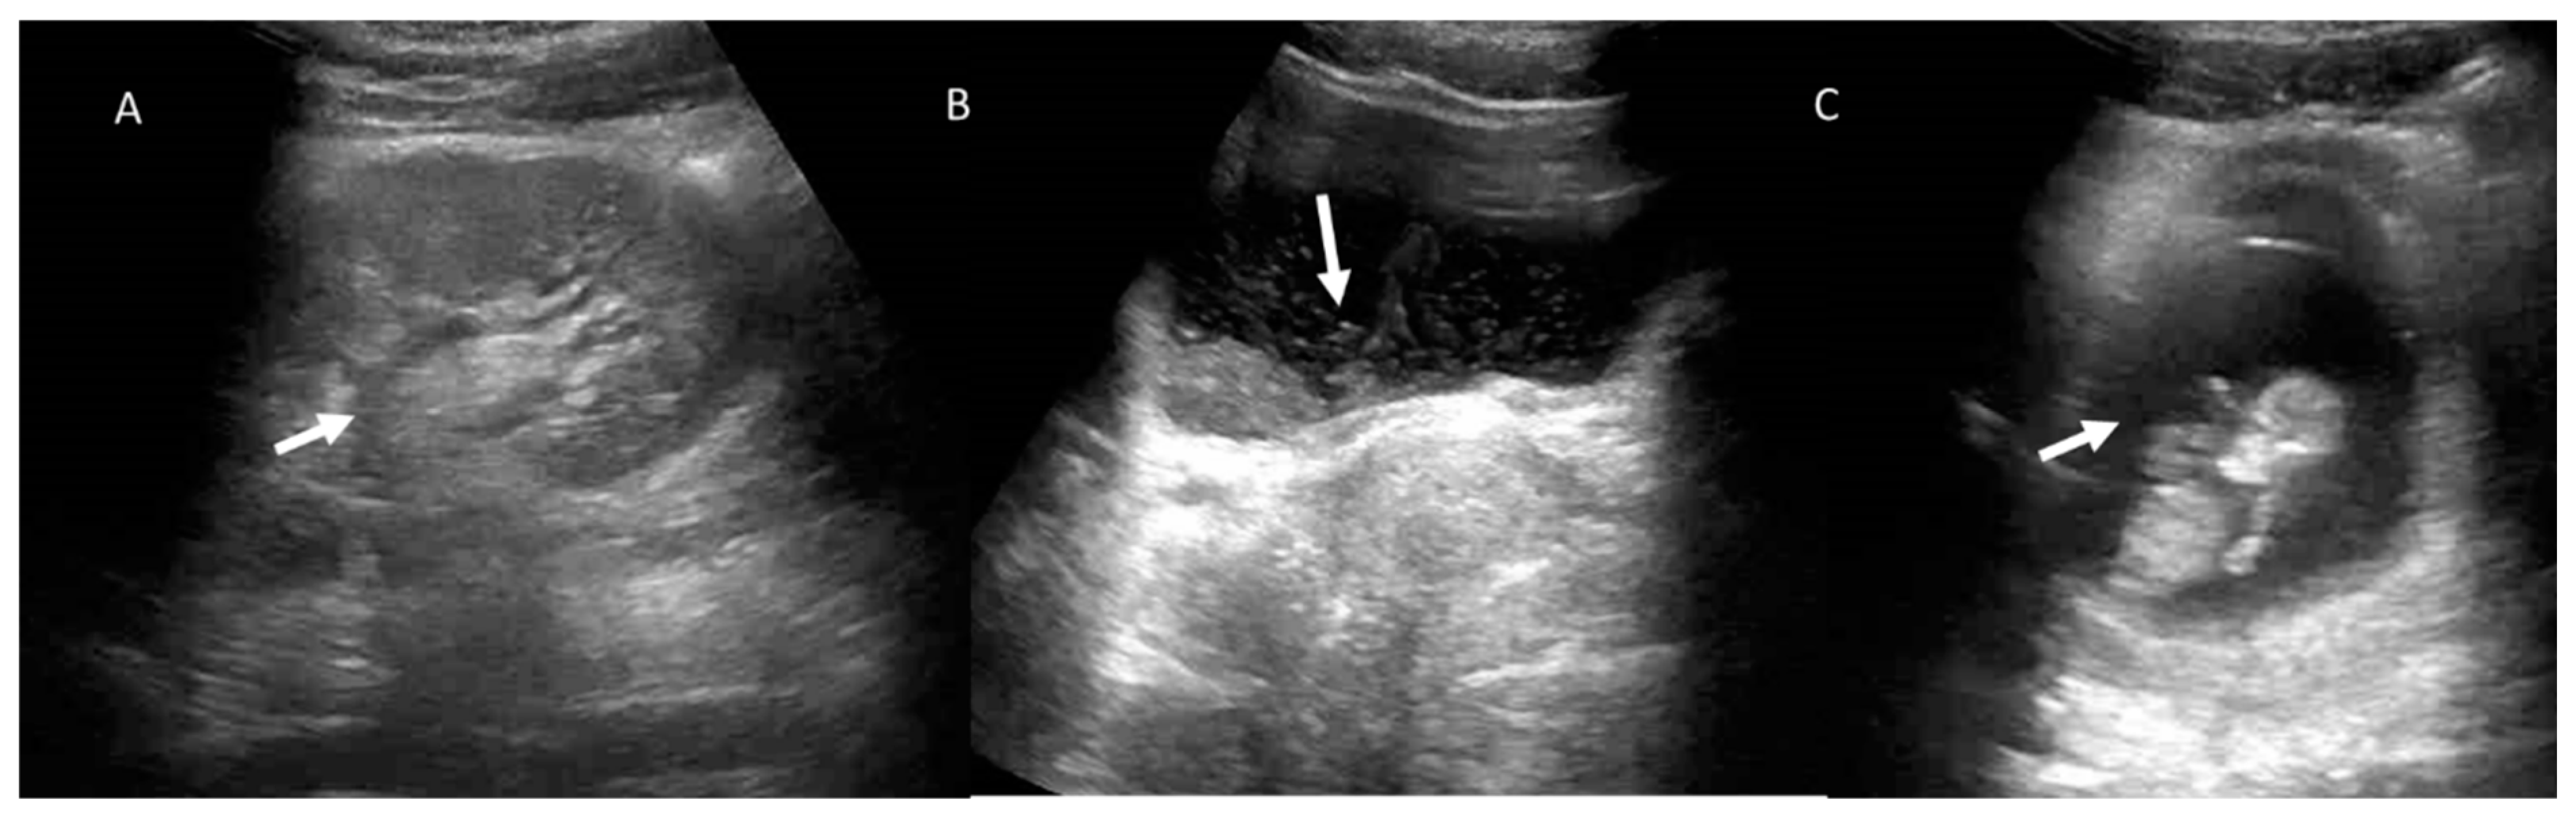

Figure 5.

Pregnant woman (C) with abdominal pain and fever. US assessment shows hydroureteronephrosis with caliceal hyperechoic material (arrows) in (A) and thickening of the bladder walls, with intraluminal hyperechoic material in (B).